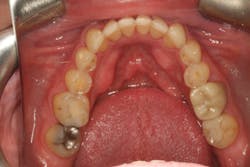

Darren remained in the provisionals for three months to allow the soft tissue to fully heal. This also allowed us to evaluate the esthetics, phonetics, occlusion, and function. The importance of provisional restorations cannot be understated, as they provide us with a trial before we place the definitive restorations.

The provisionals were especially important in this case as we had to work out the anterior guidance to be in harmony with the patient's envelope of function. When the provisional restorations were initially placed, Darren continued to feel “locked in” with the position and contours of his canines. Over several appointments, we had to slightly adjust his guidance until he was comfortable while still retaining the function and esthetics.

Finalizing a case, conservatively

Once we had confirmed the esthetics, phonetics, and function, we were ready to move forward with the definitive restorations. Photographs and impressions of the approved provisional restorations were given to the laboratory so the esthetics and occlusion that we worked out in the provisional phase could be duplicated and the information transferred to Darren’s final restorations.

The delivery of our final restorations should be the easiest part of the treatment. By the time the delivery date arrives, we have already diagnosed and treated any functional issues as well as tested our treatment plan in the provisionals. As long as the laboratory has copied our blueprint, this should be a stress-free appointment, and we should be confident in the restorations that we’re delivering.